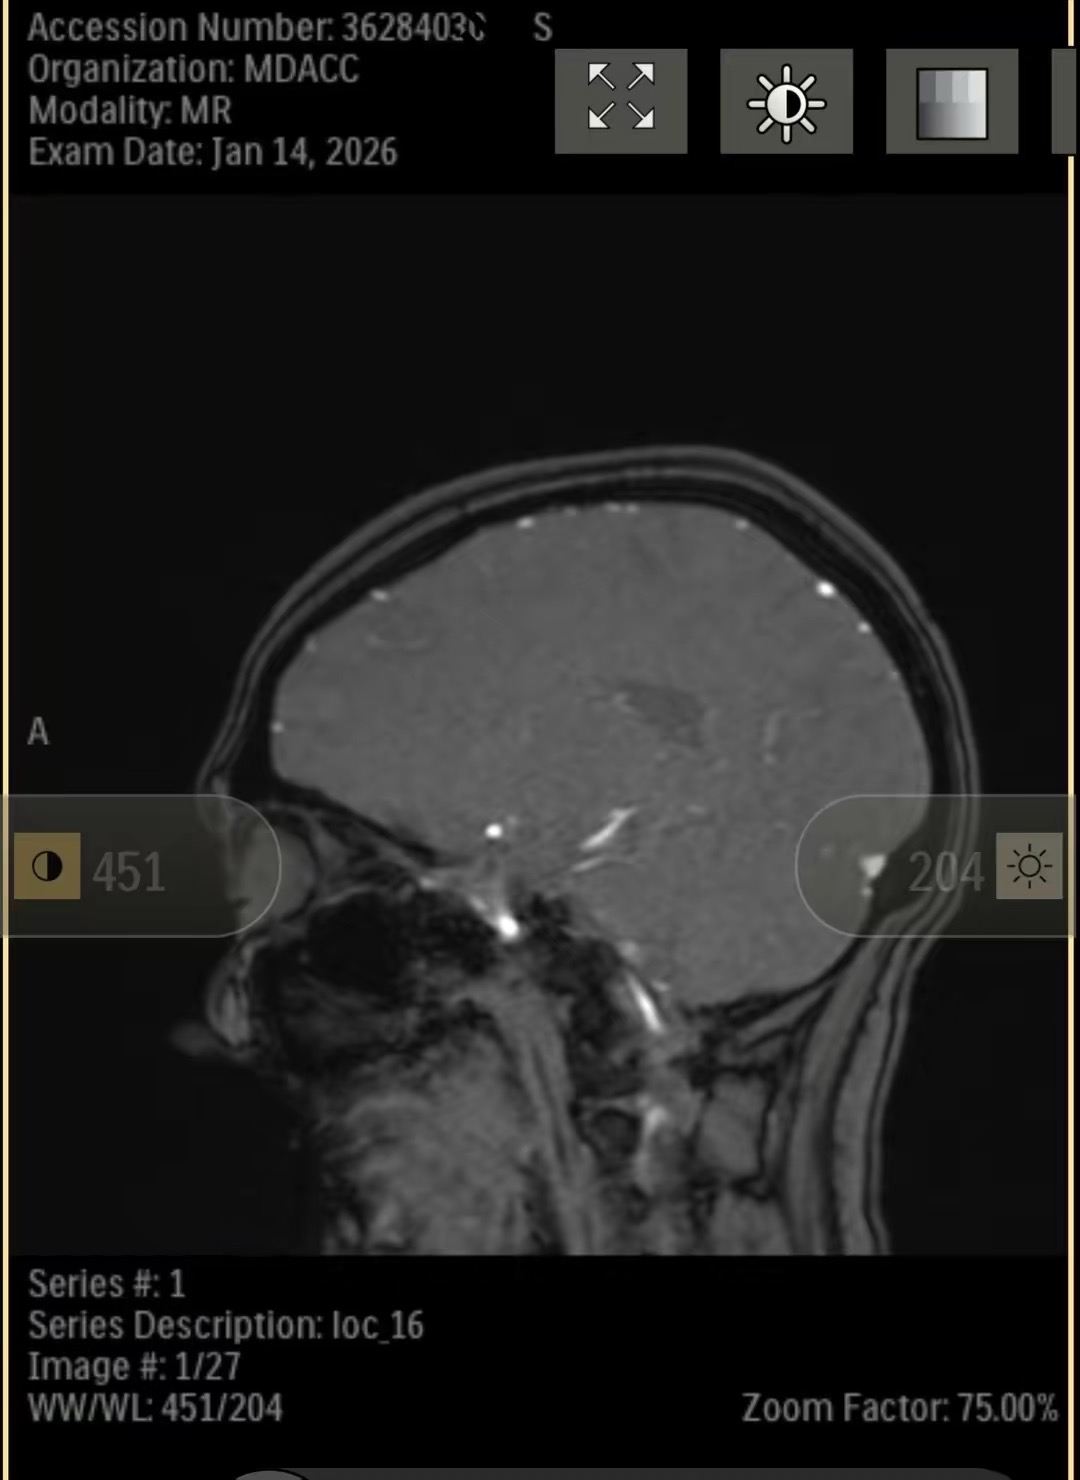

Recently, I was diagnosed with a pituitary brain tumor. Since then, my life—and my family’s—has changed in ways we couldn’t have prepared for. Between medical appointments, testing, treatment planning, and travel for specialized care, the financial and emotional weight has become heavy very quickly.